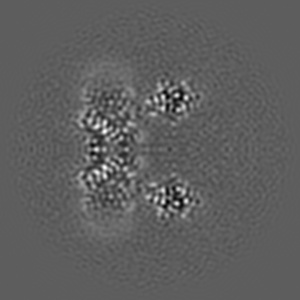

Inactivated-state cryo-EM structure of human TRPV3 in presence of tetrahydrocannabivarin (THCV) in cNW30 nanodiscs

Single-particle3.63 Å

Sample: full-length human TRPV3 in complex with THCV